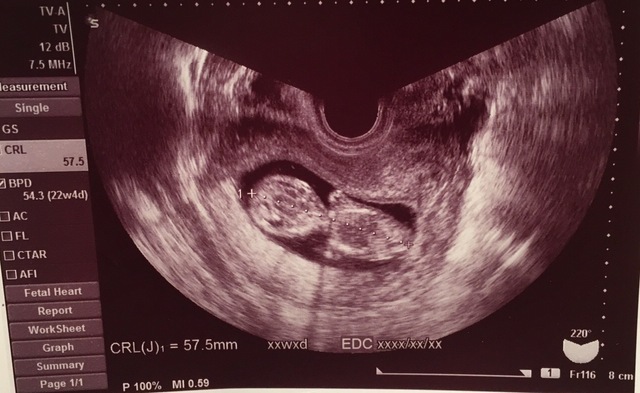

12週4日(12w4d・性別不明)|ななみかりん さん(30歳)

エコー写真撮影時のエピソード:

はじめての4dエコーです!ついこの前まで、豆粒みたいで小さい固まりだった赤ちゃんが、人の形をしているのを見て感激したことを、よく覚えています。妊娠検査薬で陽性が出て以降初めて、妊娠しているということを強く実感した思い出のエコー写真です。旦那もすごく喜んでくれて、エコー写真をずっと見ていました。